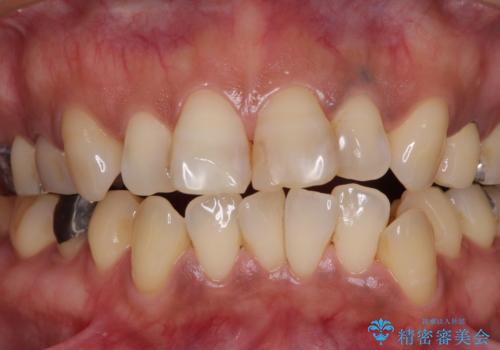

- 何度もコンポジットレジンによる修復を繰り返した結果、冷たいものがしみるようになってしまったとのことで来院された患者様です。

前歯2本が捻れている形態も気になるとのことであったので、虫歯の治療を兼ねて、オールセラミッククラウンにて補綴治療を行うこととしました。

2本とも治療前の歯髄の状態は正常でしたが、補綴治療により歯を大きく削ることになるため、歯髄が炎症を起こすリスクがあることを了解いただきました。